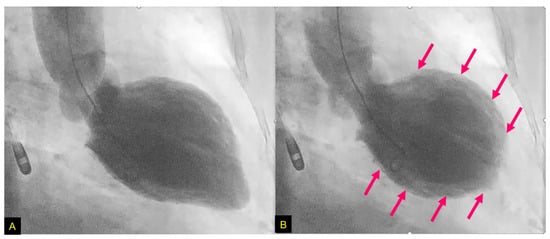

TTS(Takotsubo syndrome) was first officially reported in 1991 as a reversible cardiomyopathy that appeared to be precipitated by acute emotional stress. The majority of TTS patients were postmenopausal females and usually developed symptoms similar to those of an acute coronary syndrome. A strong emotional stressor was thought to cause a transient abnormality of LV wall motion in the apical and mid-ventricular portion without obstructive coronary artery disease with ECG changes . TTS was initially called “Takotsubo cardiomyopathy”. Although most TTS cases were described as having been caused by negative emotions, there are cases in which positive emotions, such as joy, triggered TTS. In addition, 10% of TTS patients are male.